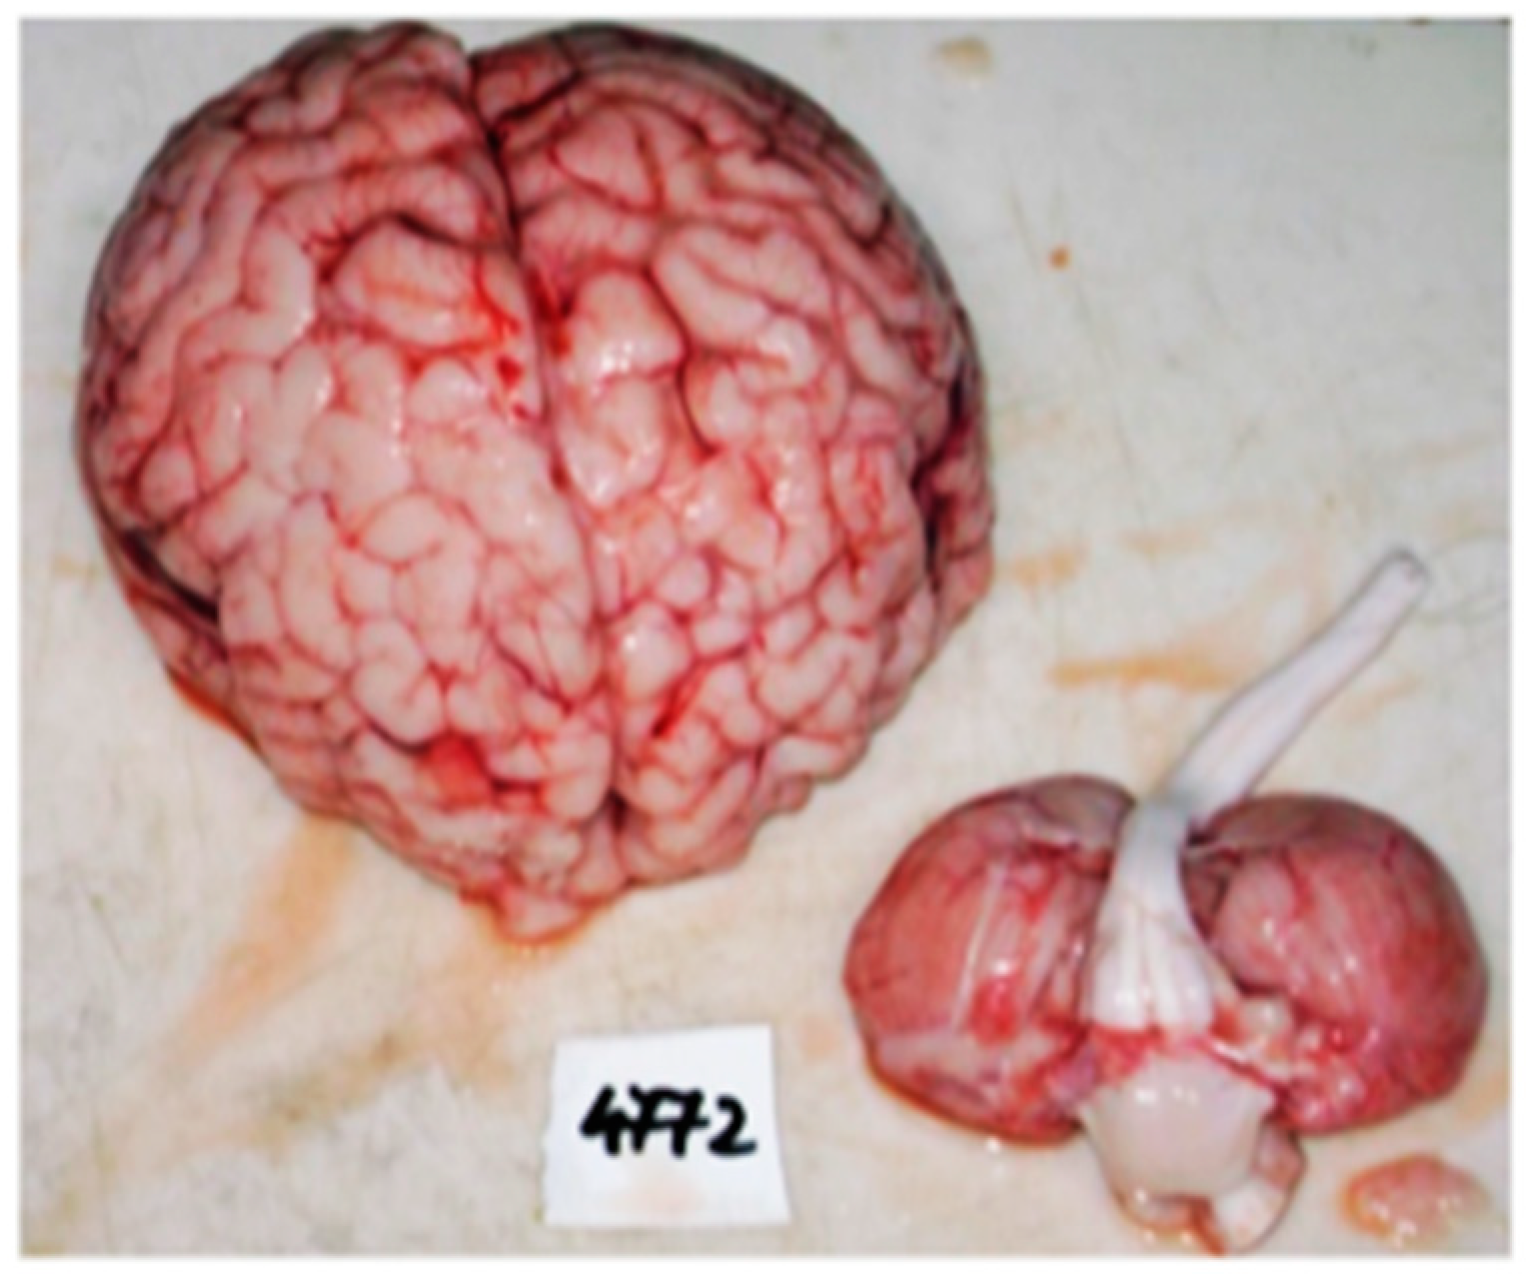

2. Case Report